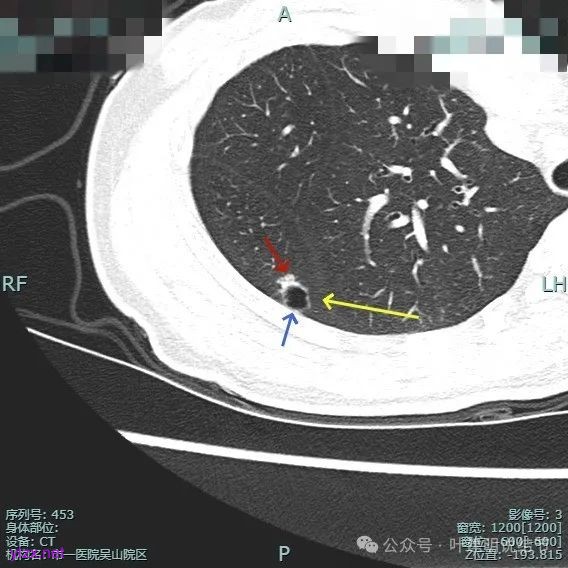

靶重建的影像上看,病灶的囊壁明显厚薄不均,有小血管进入,一侧的边似就是斜裂的样子。

囊壁有磨玻璃成分,边缘毛糙,有少许偏实性成分,仍有磨玻璃成分。

血管走向病灶,囊壁略不均。

此层见囊壁有较明显实性成分,血管进入明显。叶间裂侧平直。

混合密度,收缩力不明显,血管进入明显。

囊壁混合密度,整体轮廓清。

表面不平,血管进入,囊壁厚薄不均,紧贴叶间裂。

囊壁里面也有小空泡征。

混合密度但还是太致密,内壁毛糙不平。

病灶轮廓清楚,囊壁厚薄不均,贴着叶间裂与胸膜。